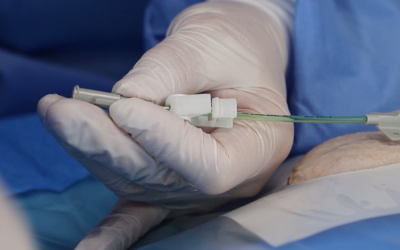

Actualmente, los reservorios, los catéteres Hickman, los PICCs, los catéteres centrales, los midlines y los catéteres cortos pueden venir con la característica “compatible con la alta presión” (llamada también CT rated o Power Injectable). Sin embargo, es fundamental comprobar siempre que nivel de alta presión y de alto flujo permiten para asegurarse que sean adecuados para la prueba que se quiera llevar a cabo.